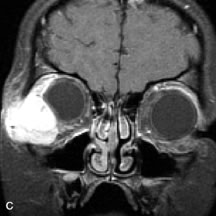

On MRI, uveal melanomas have a typical appearance that helps to differentiate them from other primary and secondary intraocular tumors as well as choroidal detachments. Pigmented melanomas are hyperintense on Tl-weighted images, hypointense on T2-weighted studies, and hyperintense on proton density–weighted examinations (Fig. 24).30,31,50,80–82 These signal characteristics have been attributed to the paramagnetic properties of melanin because of stable free radicals that shorten the T1 and T2 relaxation times. Moderate enhancement is seen on postgadolinium T2-weighted images. Gadolinium-enhanced T1-weighted images are particularly sensitive in detecting choroidal melanomas.83 MRI may be less sensitive in detecting extrascleral extension of tumor than echography performed by an experienced ultrasonographer.84

Fig. 24. A. T1- and (B) T2-weighted MR scans demonstrate a small nodular intraocular mass (arrows) that is very hyperintense on the T1-weighted scan and hypointense on the T2-weighted image. This signal intensity pattern is due to the presence of free radicals within melanin granules. C and D. Postcontrast fat-suppressed T1-weighted scans demonstrate homogeneous intense enhancement of the lesion and no evidence of seleral penetration or optic nerve invasion.